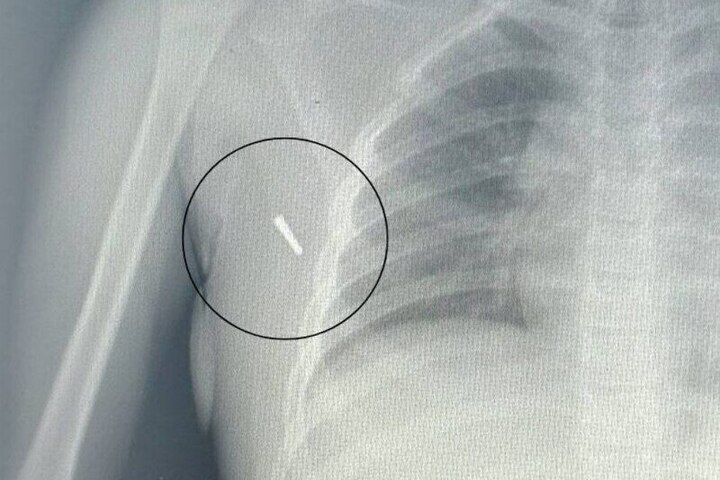

Врачи Артемовской городской больницы спасли жизнь восьмилетней девочке, в тело которой в результате ДТП проник наконечник ртутного термометра. Об этом сообщили в медицинском учреждении.

Инцидент произошел 18 июля. По данным медиков, ребенок ехал в автомобиле с установленным в подмышку градусником – в это время транспортное средство попало в дорожно-транспортное происшествие. От удара наконечник градусника отломился и глубоко проник в мягкие ткани подмышечной впадины.

«Ситуация была крайне неординарной. Мы имели дело не просто с механическим повреждением, но с потенциальной угрозой отравления парами ртути. Девочка поступила в приемное отделение в сопровождении родителей, травматологи немедленно приняли решение об извлечении инородного тела», – рассказали в приемном покое стационара.

Операция по извлечению наконечника прошла успешно. Медики провели полный комплекс обследований – включая рентген и анализы на наличие интоксикации. После вмешательства девочка осталась под наблюдением в стационаре.